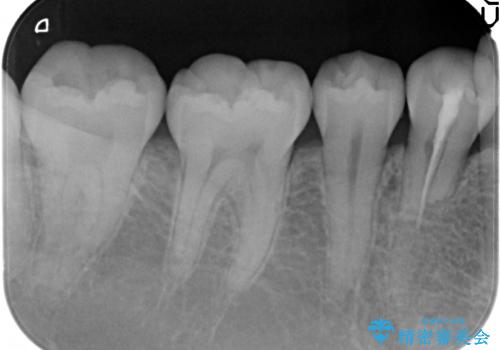

レントゲンを撮影したところ、右下4は神経のない歯で、外部吸収といって、根がだんだん短くなり、やがて抜けてしまう症状になっていました。また、アンキローシスを起こしている可能性があるため、動かない可能性が高い状態でした。

矯正治療で右下を抜歯し、スペースを天然の歯でつめる矯正治療を行いました。

治療期間はかかりましたが、右下4が一生もつとは思えない状態でしたので、人工物を入れないようにすることができました。

矯正治療をしない場合は、右下はブリッジかインプラントが必要になっていたと思います。